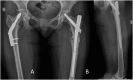

A 27 years old sedentary woman presented bilateral femoral neck stress fractures after having clinically recovered from anorexia nervosa and was treated with bilateral internal fixation.

Conclusion: Although light exercise is usually considered after recovery from anorexia nervosa to improve bone quality, this case of a sedentary patient suggests that weight gain, per se, could increase the stress fracture risk. Because of the physiological and psychological characteristics, these patients should be treated with a multi-disciplinary approach.